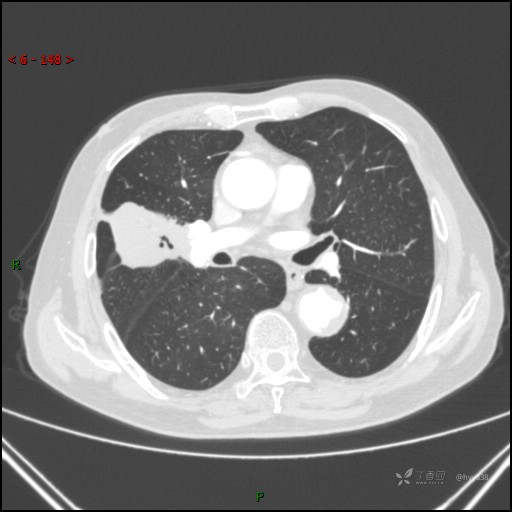

胸部CT肺窗